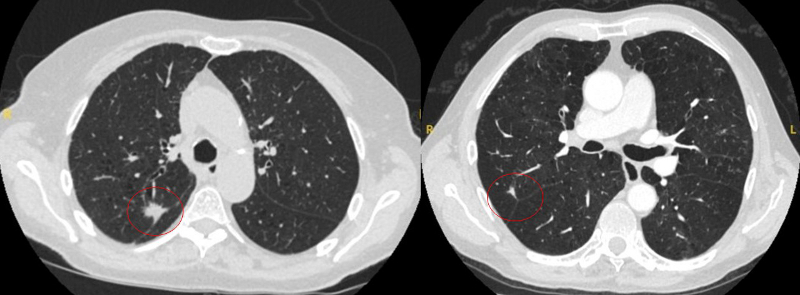

[Figure caption and citation for the preceding image starts]: Computed tomography (CT) showing examples of malignant perifissural nodules. Note the spiculated edge of the nodules and the evident retraction of the adjacent fissure. Both resection tissue analyses confirmed adenocarcinoma of lungFrom the collection of Dr George Tsaknis, MD, PhD, FRCP(London), MRQA, MAcadMEd, PGCert; used with permission [Citation ends].